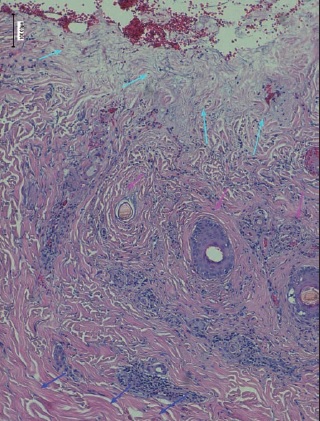

La realización de biopsias pre y postratamiento en 3 de los pacientes permitió observar 2 casos de desbridamiento parcial de la zona necrótica, siendo 1 caso una quemadura de tercer grado en dorso de mano que precisó de injerto (Fig. 25 a 34, caso 9), y el otro una quemadura previamente tratada con Flammazine Cerio® (Fig. 35 a 45, caso 12). En el tercero de los pacientes biopsiados apreciamos desbridamiento histológico completo de la zona necrótica con preservación de la dermis sana (Fig. 46 a 50, caso 11). Como hallazgos significativos, en las 3 muestras postratamiento evidenciamos un infiltrado inflamatorio linfocítico perivascular (Fig. 36, 40 y 48).

Si bien planteamos la realización de las biopsias para comprobar la correlación clínico-histológica del diagnóstico de profundidad de la quemadura, evidenciamos una disparidad de criterio en la eficacia del desbridamiento según se considere el aspecto clínico o el histológico. Así, aunque nos pareció clínicamente que el desbridamiento fue completo en todos los casos, constatamos mediante la histología que no era así. Dos de las 3 muestras presentaron desbridamiento histológico incompleto. Sin embargo, 1 de ellas fue una quemadura de tercer grado que precisó injerto y en la que la reaplicación del producto no hubiese supuesto ninguna ventaja; en la otra, la quemadura epitelizó espontáneamente sin necesidad de mayor desbridamiento, por lo que nuevamente la reaplicación no parece que hubiese supuesto ventajas añadidas. De estos resultados podemos deducir que la valoración clínica de la eficacia del desbridamiento, aunque no coincide con la valoración histológica y tiende a sobreestimar la capacidad desbridante de Nexobrid®, sí parece suficiente para decidir la reaplicación del producto, sin precisar biopsias que determinen la eficacia del desbridamiento.

Otro hallazgo significativo de nuestro estudio es el incremento del infiltrado inflamatorio tras el tratamiento (Fig. 36, 40 y 48). Sin embargo, no podemos afirmar que sea consecuencia del tratamiento enzimático ya que no realizamos comparación con zonas de quemadura no sometidas a tratamiento con Nexobrid®. Además, en la literatura existe referencia al infiltrado neutrofílico típico que existe en la zona intermedia de la quemadura (región histológica comprendida entre la zona sana y la zona necrótica de la quemadura), pero el evidenciado en nuestro estudio es un infiltrado linfocítico perivascular que, hasta donde nosotros sabemos, no aparece mencionado en ningún estudio publicado sobre el desbridante Nexobrid®.(21) Aunque desconocemos si este infiltrado es originado o potenciado por el tratamiento con Nexobrid® o bien debido exclusivamente a la progresión de la quemadura, sería necesario estudiar si el posible incremento del infiltrado inflamatorio guarda correlación con la velocidad de curación o con el pronóstico a largo plazo, o bien es únicamente el resultado de la evolución fisiopatológica de la quemadura y no existen diferencias con el infiltrado evidenciado en las quemaduras no tratadas con Nexobrid®.

Los estudios histopatológicos de nuestra serie revelaron una buena correlación entre la valoración clínica de la profundidad de la quemadura con los resultados histológicos, así como la presencia de desbridamiento histológico parcial que se había diagnosticado clínicamente como completo, sin implicaciones clínicas relevantes que justifiquen el uso de biopsia para la evaluación de la calidad del desbridamiento.